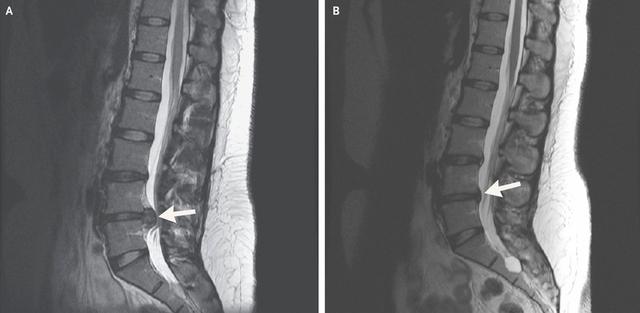

Cervical Spine Treatment Cases 腰椎治療案例 #今天來聊巨大骨刺為何可以吸收回去! #椎間盤突出需要多久才能吸收呢? #馬尾神經症候... 2020.09.08 #典型假性坐骨神經痛 #原來是梨狀肌症候群 #核磁共振排除椎間盤突出 #抽絲剝繭真相大... 2020.08.13 #嚴重椎管狹窄醫案 #感謝台北林大哥熱情見證 #從寸步難行到輕快漫步 #鍛鍊多裂肌的重... 2020.08.12 #椎間盤突出可以吸收回去嗎 #微針治療原理是什麼 #何時一定要接受神外開刀 #一張圖秒... 2020.08.11 #感謝花蓮鄉親林大姐熱情見證 #一分鐘認識椎管狹窄 #原本痛到無法走路打算開刀了 #脊... 2020.08.01 #感謝新莊區林先生熱情見證 #椎間盤突出跟纖維環裂隙的關係 #纖維環破裂突出可以不... 2020.07.28 #逆轉勝又一發case #原本疼痛一年多想說一定要手術治療了 #八週治療後症狀全部消失 #... 2020.07.25 #巨大椎間盤突出一定要開刀嗎 #除了開刀以外的選擇 #感謝台北市吳先生熱情見證 2020.07.24 #腰椎滑脫的疼痛心酸誰人知啊 #一分鐘瞭解腰椎滑脫 #哪一種情況需要積極開刀 #要如何... 2020.07.21 #巨大椎間盤脫垂一定要開刀嗎? #感謝新店林先生熱情見證受訪 #西醫手術有那些選擇... 2020.07.02 #纖維環裂隙AnnularFssures #MRI看起來不嚴重卻嚴重困擾患者 #感謝桃園市蕭先生熱情見... 2020.06.19 #骨刺有可能吸收回去嗎?? #疼痛超過六年的特殊案例探討 #MRI核磁共振前後對比 #感謝... 2020.06.14 #坐骨神經痛一定要開刀嗎 #突出的骨刺真的可以自己吸收嗎 #最新英國醫學期刊BMJ的看... 2020.05.30 #骨刺跟突出髓核有可能吸收回去嗎?? #特殊案例探討 #核磁共振一年後對比 2020.05.29 #從醫以來第一次碰到薦椎Tarlov cyst囊腫#左邊紅色圈圈是個案,右邊是國外案例#腰... 2020.05.23 ← 上一頁 10 11 12 13 14 下一頁 →